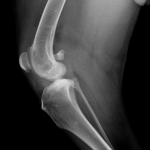

Ελεγχος Προγνωση και Αντιμετωπισεις,ρηξης προσθιου χιαστου συνδεσμου στο σκυλο.

Μια παθηση του σκυλου που απαιτει κλινικη εκτιμηση αλλα και απεικονισεις,(ακτινολογικη-CT-MRI)κατα περιπτωση.Σχετικα συχνη παθηση με προδιαθεση καποιων φυλων,στην εμφανιση του προβληματος.

Στη χειρουργικη αντιμετωπιση του,υπαρχουν αρκετες τεχνικες και η επιλογη εξαρταται απο πολλες παραμετρους,προεγχειρητικες μετρησεις και ανατομικα στοιχεια.